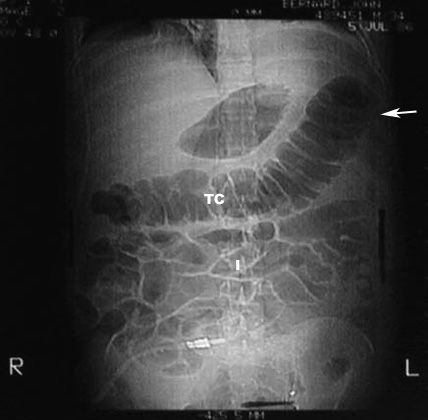

What are the anticipated imaging findings of acute pancreatitis in plain film?

- Abdominal x-ray is not diagnostic, but may show:

- Calcification in the pancreas

- Mass from a pseudo cyst

- Sentinel loop: Dilatation of duodenum

- Colon cut off: Dilated colon to the mid-transverse colon. No air seen beyond splenic flexure. This is due to extension of inflammation along mesocolon.

- Diffuse ileus ( small bowel dilatation) most commonest

- Left pleural effusion